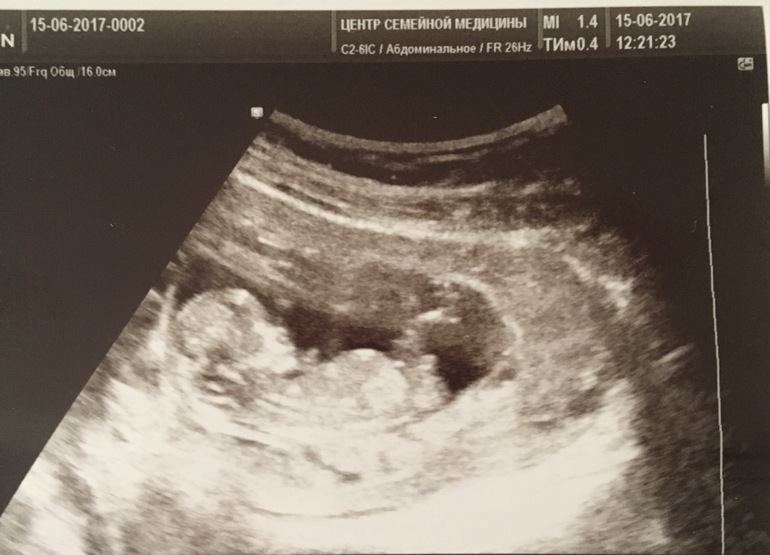

Скрининг проводила на сроке 11+4, обычно делают в 12 недель, но мой врач назначила меня так. 2 недели назад по УЗИ мы были 22 мм, думала не дотянем до 45 мм, а выросли уже до 55 мм, когда они успевают так быстро расти?)) Счастливы с мужем до безумия, но мой страх все никак не отходит, когда же я уже спокойно начну наслаждаться своей беременностью. P.S. Нам узистка предположила мальчика, сразу сказала, что на таком сроке мы только предполагаем пол, а не устанавливаем. Но по своему опыту вижу мальчика. Но нам главное, чтобы здоровый малыш был)) Еле сдержала слезы на УЗИ, но я старалась держать себя в руках))